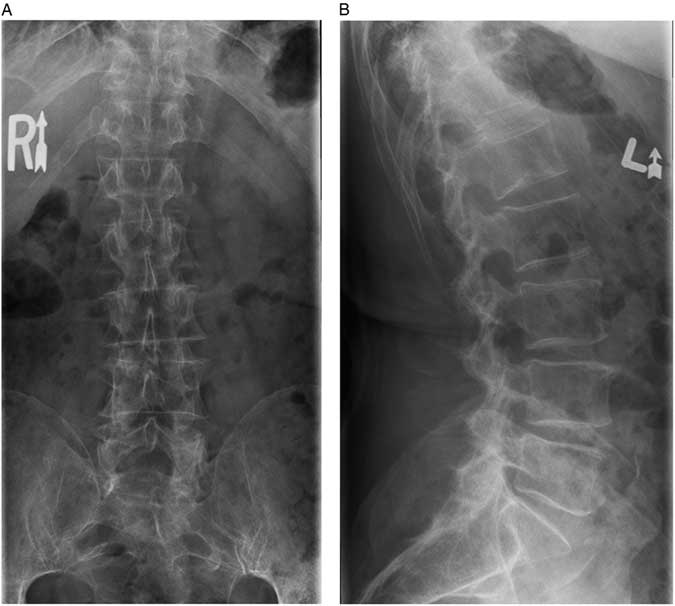

The family physician ordered thoracolumbar spine radiographs, which subsequently were reported as being free of any lesion or fracture (Figure 1). His past medical history was remarkable for a transient ischemic attack and hypothyroidism for which the patient was taking clopidogrel bisulfate, 75 mg once daily, and levothyroxine, 100 μg once daily, respectively. The patient’s routine laboratory investigations over the previous year demonstrated normal vitamin D, sodium, potassium, and chloride levels as well as a normal urinalysis. Two years prior, the patient did have a transient pancytopenia, which, after resolving spontaneously, was not investigated further. It was recommended by the family physician that the patient try conservative measures for his lower back pain, including the use of nonsteroidal anti-inflammatory medication.

Figure 1 A) Anterior-posterior and B) lateral radiographs of the thoracolumbar spine acquired in the community. No spinal injuries were noted.